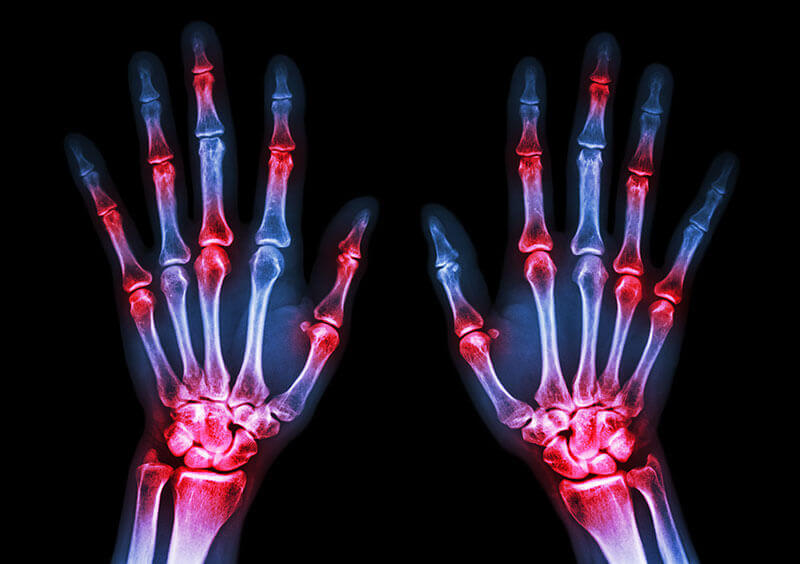

Poliartrita reumatoida este o boala autoimuna care poate provoca dureri articulare si leziuni in intregul corp. Leziunile articulare cauzate de aceasta afectiune apar de obicei pe ambele parti ale corpului. Deci, daca o articulatie este afectata intr-unul dintre brate sau picioare, aceeasi articulatie la celalalt brat sau picior va fi probabil afectata si ea. Aceasta este o modalitate prin care medicii disting poliartrita reumatoida de alte forme de artrita, cum ar fi osteoartrita.

Poliartrita reumatoida este o boala autoimuna in care sistemul imunitar al organismului (care protejeaza in mod normal sanatatea lui prin atacarea substantelor straine precum bacteriile si virusii) ataca in mod eronat articulatiile. Acest lucru creeaza inflamatie care provoaca tesutul aflat in interiorul articulatiilor (tesut sinovial) sa se ingroase, ducand la umflaturi si dureri in articulatii si in jurul acestora. Tesutul sinovial produce un fluid care lubrifiaza articulatiile si le ajuta sa se miste usor.Daca inflamatia nu este controlata, aceasta poate afecta cartilajul, tesutul elastic care acopera capetele oaselor dintr-o articulatie, precum si oasele insele. In timp, exista o pierdere a cartilajului, iar distanta dintre oase poate deveni mai mica. Articulatiile pot deveni libere, instabile, dureroase si isi pot pierde mobilitatea. Deformarea articulatiilor poate, de asemenea, sa apara. Deteriorarea articulatiilor nu poate fi inversata si deoarece poate aparea devreme, medicii recomanda diagnosticarea precoce si tratamentul agresiv pentru a controla poliartrita reumatoida.

Poliartrita reumatoida afecteaza cel mai frecvent articulatiile mainilor, picioarelor, incheieturilor mainilor, coatelor, genunchilor si gleznelor. Efectul este de obicei simetric, insemnand ca daca mana dreapta este afectata, cel mai probabil va fi si cea stanga.

In stadiile incipiente, persoanele cu poliartrita reumatoida pot sa nu aiba initial roseata sau umflaturi la nivelul articulatiilor, dar pot prezenta sensibilitate si durere. Cazul tipic al poliartritei reumatoide incepe insidios, cu dezvoltarea lenta a semnelor si simptomelor de la saptamani la luni. Adesea, pacientul observa mai intai rigiditatea in una sau mai multe articulatii, de obicei insotite de durere la miscare si sensibilitate in articulatie. Numarul de articulatii implicate este foarte variabil, dar aproape intotdeauna procesul este in cele din urma poliarticular, implicand cinci sau mai multe articulatii. Ocazional, pacientii se confrunta cu o boala poliarticulara exploziva care are loc in decurs de 24 pana la 48 de ore. Un alt simptom comun este o prezentare palindromica, in care pacientii descriu umflarea uneia sau a doua articulatii, care poate dura cateva zile pana la saptamani, apoi poate disparea complet, facandu-si prezenta mai tarziu in aceleasi sau in alte articulatii.Cel mai adesea sunt implicate articulatiile proximale interfalangiene si metacarpofalangiene ale mainilor, incheieturilor si articulatiilor mici ale picioarelor, inclusiv articulatiile metatarsofalangiene. Umerii, coatele, genunchii si gleznele sunt de asemenea afectate la multi pacienti. Articulatiile distal interfalangiene sunt in general lipsite de aceasta afectiune.

Umflaturie articulare simetrice sunt caracteristice poliartritei reumatoide care a fost persistenta pentru o perioada de timp. Cu toate acestea, atunci cand doar cateva articulatii sunt afectate la inceputul bolii, este posibil ca simetria sa nu fie vazuta si nu trebuie sa impiedice diagnosticarea poliartritei. Palparea atenta a articulatiilor poate ajuta la distingerea umflarii si inflamatiei articulare. Umflarea articulatiilor proximale interfalangiene si metacarpofalangiene ale mainilor este o descoperire obisnuita. Incheieturile, coatele, genunchii, gleznele sunt alte articulatii frecvent afectate, iar umflarea este detectata cu usurinta.Ocazional, articulatiile inflamate se vor simti calde la atingere. Inflamatia, deformarea structurala sau ambele pot limita gama de miscare a articulatiei. In timp, unii pacienti cu poliartrita reumatoida dezvolta deformari la nivelul mainilor sau picioarelor. Examenul fizic poate dezvalui alte semne, cum ar fi noduli reumatoizi sau febra scazuta.